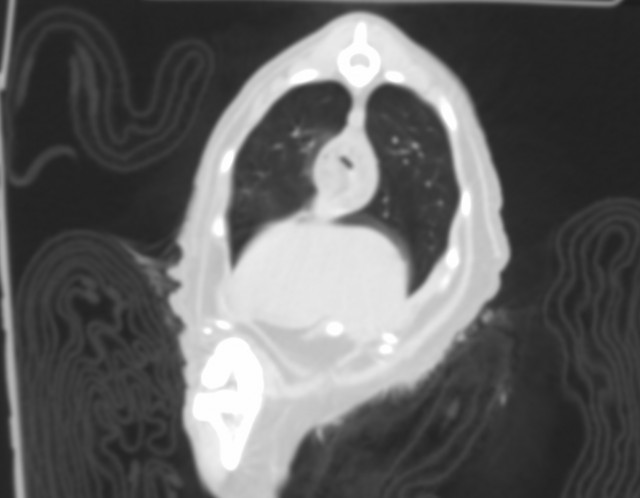

雑種ネコ15歳 呼吸困難と食欲減退を主訴に来院。

レントゲン検査にて肺または食道の異常が疑われたため、無麻酔でCT検査を実施。(本症例はおとなしい性格のため実施可能であった)

検査の結果、食道腫瘤と確認された。

飼い主様は病理検査を含めた精査は高齢のため希望されず、流動食の給餌で経過観察となった。